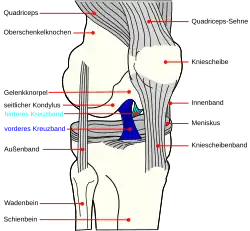

Von einem Kreuzbandriss oder einer Kreuzbandruptur spricht man bei einem unvollständigen (partiellen) oder vollständigen (kompletten) Riss (Ruptur) eines oder beider Kreuzbänder. In den meisten Fällen ist das vordere Kreuzband (Ligamentum cruciatum anterius) betroffen. Durch Überschreiten seiner Reißfestigkeit kommt es zu Einriss oder Abriss des Bandes, eventuell mit Ausriss des knöchernen Ansatzes (Insertion).

In den wenigsten Fällen sind Kreuzbandrisse isolierte Verletzungen. Die Rupturen werden meist von anderen Läsionen weiterer Bänder und der Menisken begleitet.[1] Es können zwei Arten von Kreuzbandrissen unterschieden werden:

Vorderes Kreuzband

Die Verletzung des vorderen Kreuzbands entsteht typischerweise durch einen Richtungswechsel. Häufig liegt eine Drehbewegungsstellung des Unterschenkels nach außen mit Valgusbeugungsstress oder eine Drehbewegungsstellung nach innen mit Varusbeugungsstress vor. Auch zu starke Streck- oder Beugebewegungen (Hyperextension beziehungsweise Hyperflexion) können ein Auslöser sein. In den überwiegenden Fällen handelt es sich um Sportverletzungen. Besonders häufig treten solche Verletzungen (Traumata) unter sogenannten „Stop-and-Go“-Sportarten (z. B. Tennis oder Squash) und bei Mannschaftssportarten (z. B. Fußball, Football, Handball, Hockey oder Basketball) – oft auch unter Fremdeinwirkung – auf. Auch beim Skifahren – vor allem wenn der Tal-Ski nach außen dreht, der Körper aber über dem Berg-Ski fixiert bleibt – sind Rupturen des vorderen Kreuzbandes eine häufige Art der Verletzung. Der über die Valgus- und Innenrotationsstellung laufende Verletzungsmechanismus beim Skifahren wird auch als „Phantomfuß-Mechanismus“ bezeichnet.[1][8] Ein Riss kann auch durch eine Auskugelung der Kniescheibe (Patellaluxation) mit plötzlichem Stabilitätsverlust des Kniegelenks bedingt sein.

Durch den Ausfall (Insuffizienz) des vorderen Kreuzbandes ist die Funktion eines der beiden zentralen passiven Führungselemente (primäre Stabilisatoren[9]) des Kniegelenks gestört. Daraus resultiert eine pathologische Bewegungsfreiheit des Schienbeinkopfes nach vorne (ventral), der sogenannte „Tibiavorschub“. Gelenkkapsel, Seitenbänder, hinteres Kreuzband und Menisken werden vermehrt beansprucht, um den Schienbeinvorschub zu bremsen. Es kommt zu einer Überdehnung der Bandstrukturen. Bei Zunahme des Schienbeinvorschubs kommt es zu Knorpelschäden. Diese sind unter anderem dadurch bedingt, dass der Knorpel einer deutlich höheren Belastung ausgesetzt ist. Eine höhere Belastung bedeutet in so einem Fall eine frühzeitige Abnutzung mit Ausbildung einer Arthrose. Den vorderen Kreuzbandriss begleitende Verletzungen der Menisken und des Knorpels potenzieren das Risiko einer Arthrose.[10]